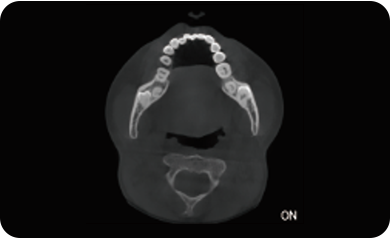

超能去伪 至臻影像

临床样片